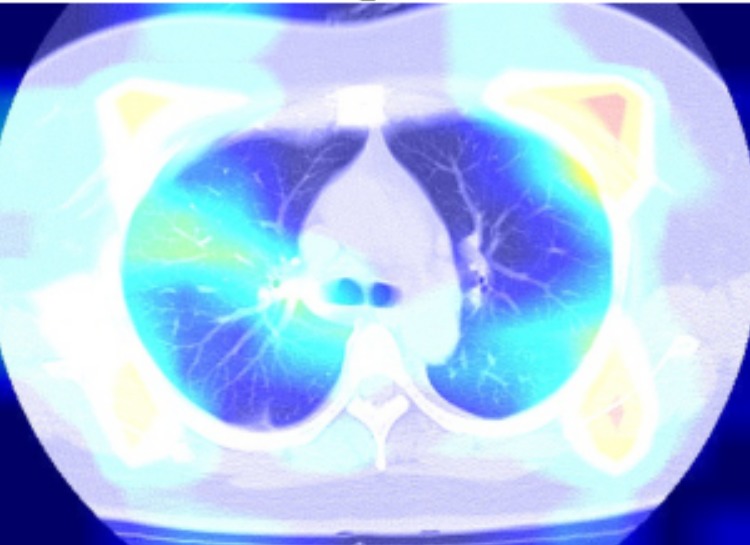

With COVID-19 tests being carefully rationed out and there being multiple scarcities, patients may not have access to a traditional test. Our software can diagnose a patient purely on a CT scan, eliminating the need for single use tests. We used the COVID-19 Lung CT Scans by LuisBlanche on Kaggle.

Our web app has a form for submitting patient data and uploading a CT scan image. We then pass the pixel data to our server, which runs several Tensorflow models. We then take the average confidence of all the models, and return the prediction to the browser. You can test it with the CT Scan images in the Devpost Gallery.